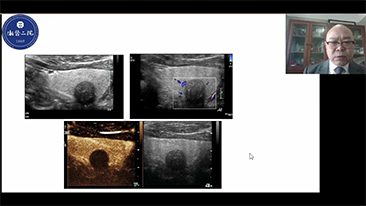

Para las lesiones hepĂĄticas focales, como el hemangioma o el cĂĄncer de hĂgado, el diagnĂłstico por imĂĄgenes mediante ecografĂa con contraste cumple un papel importante. La tecnologĂa de diagnĂłstico por imĂĄgenes con contraste UWN+ (no lineal ultraancha) puede ayudar a obtener una mejor penetraciĂłn, una mayor relaciĂłn contraste-tejido, con un IM mĂĄs bajo y una observaciĂłn del tiempo de perfusiĂłn mĂĄs prolongada.